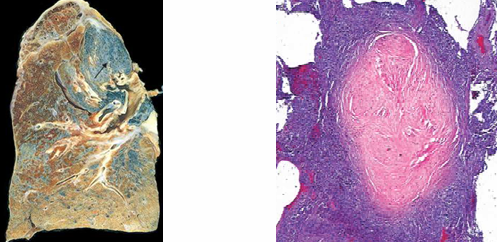

Silicosis